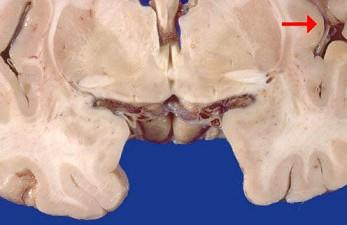

问题 如图箭头所示为大脑哪个部位 ( )

选项 A、岛叶 B、海马 C、颞叶 D、尾状核 E、壳核 一、单项选择题

答案 A